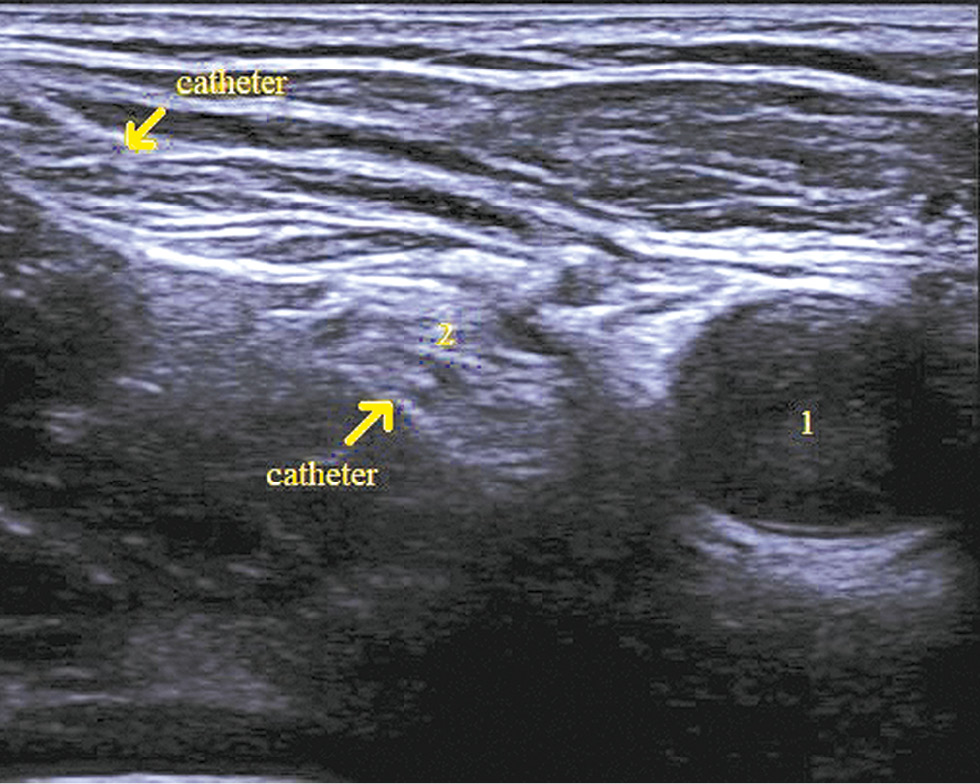

Using a catheter-through-needle technique, a perineural catheter was positioned at 2 cm from the femoral nerve (Fig. 3).

Fig. 3. Femoral nerve catheter.

Note. 1 — femoral artery, 2 — femoral nerve.